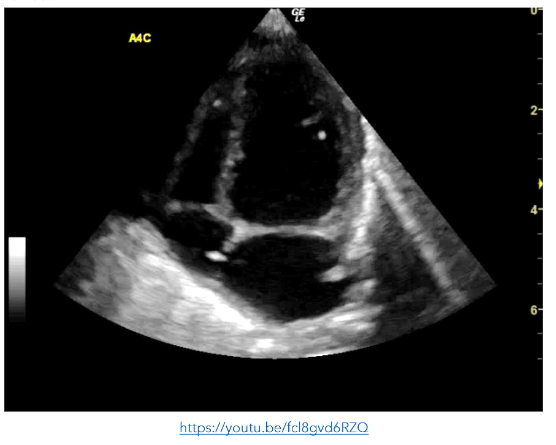

Figure 7: A4C view showing small echogenic masses in the left ventricle, right ventricle and right atrium consistent with septic emboli

Figure 8: SC view showing small echogenic masses in the left ventricle, right ventricle and right atrium consistent with septic emboli. The right atrium is poorly visualised and cannot be assessed https://youtu.be/awqHN68tV2g